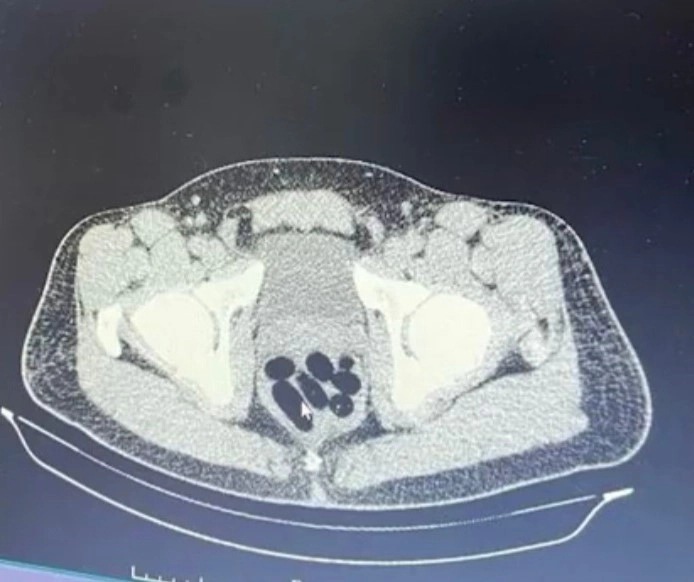

Kayseri’de polis ekipleri tarafından düzenlenen operasyonda, bir şahsın midesinden 1 kilo 134 gram uyuşturucu çıktı.Kayseri İl Emniyet Müdürlüğü Narkotik Suçlarla Mücadele Şube Müdürlüğü ekipleri, uyuşturucu madde ticareti yapan şahıslara yönelik analiz çalışması yürüttü. M.R.B’nin (23) kente uyuşturucu madde getireceğini tespit eden ekipler operasyon düzenledi. Gözaltına alınan şahsın hastanedeki iç beden muayenesinde 77 adet kapsül şeklinde 1 kilo 134 gram narkotik madde ele geçirildi. Şahsın midesindeki maddeler cerrahi müdahale ile çıkarılırken, şahıs hakkında "uyuşturucu madde ticareti yapmak" suçundan adli işlem başlatıldı.